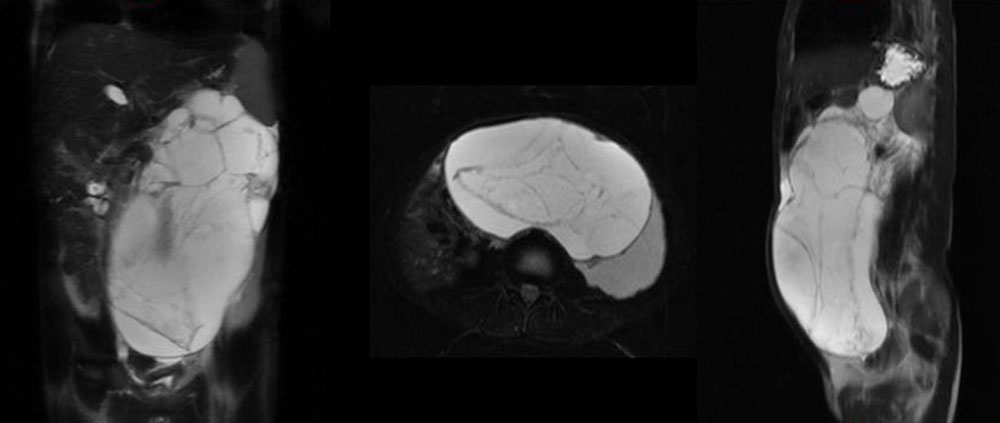

A classic lymphatic malformation consists of a circumscribed lesion with cystic dilations of lymphatic vessels of varying size, a thin wall with many septations, and is filled with lymph fluid without drainage into the normal lymphatic system. Lymph fluid (clear yellow or milky white in the case of chyle) forms and collects in the cysts, causing the cysts to grow to different sizes. When the cyst size exceeds 2 cm (in some definitions 1 cm), it is referred to as a macrocystic LM; smaller cysts are referred to as microcystic LMs. In many cases cysts of both groups are present (then called “mixed cystic LM” according to the ISSVA classification). Small feeding blood vessels usually run in the cyst walls; these may bleed during surgical procedures and occasionally cause the LM to be misclassified as a mixed vascular malformation (e.g., lymphatic-venous malformation LVM). Nevertheless, a true LVM may also be present.

A large retroperitoneal lymphatic malformation may affect bowel passage or bladder capacity and emptying.